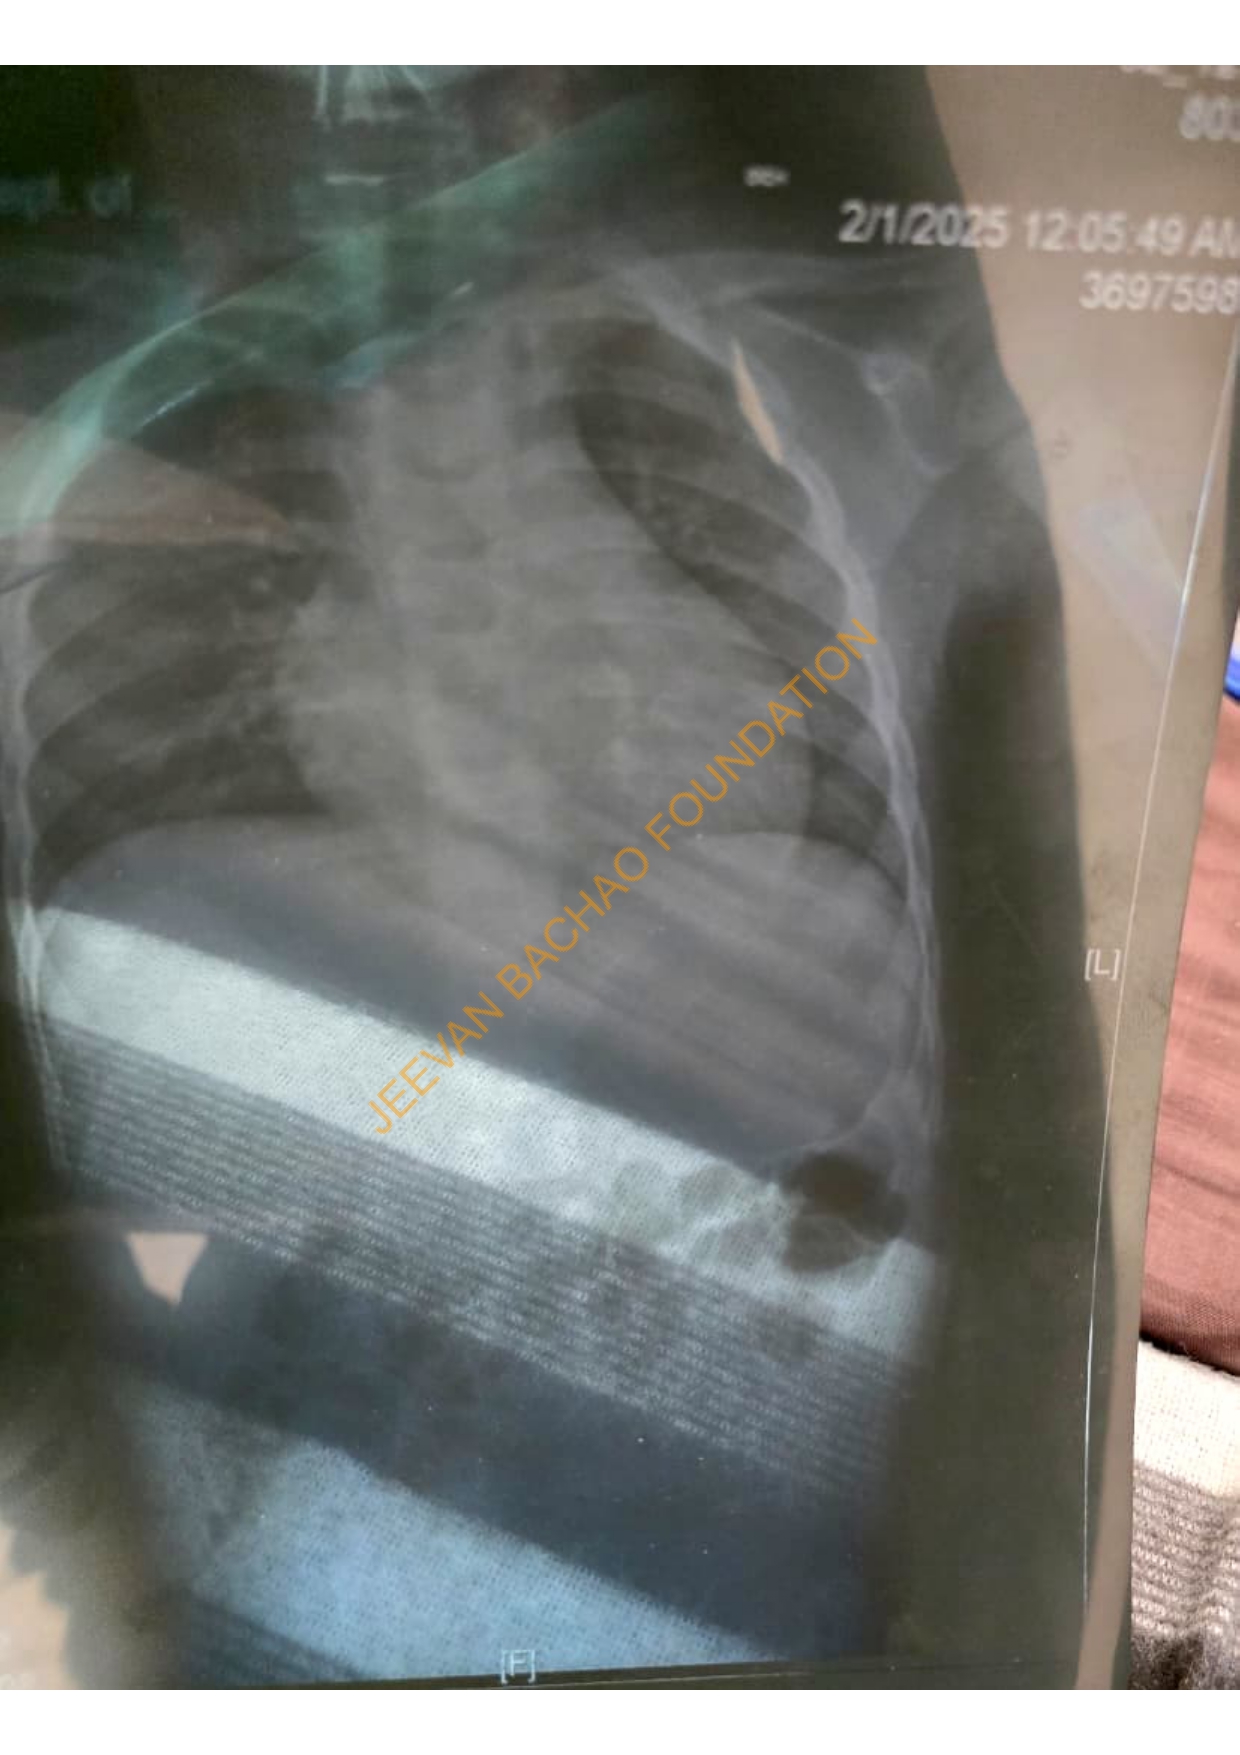

I hope this message finds you well. My name is Vinnay Kumar, I am 11 Years Old old only,basically I belong from Uttar Pardesh, and I am reaching out to you with a heavy heart but hopeful spirit. Recently, I was diagnosed with Bone Cancer (Shoulder), and I am now embarking on a challenging journey towards recovery I am humbly reaching out to request your support in the form of a donation to assist with my medical expenses.